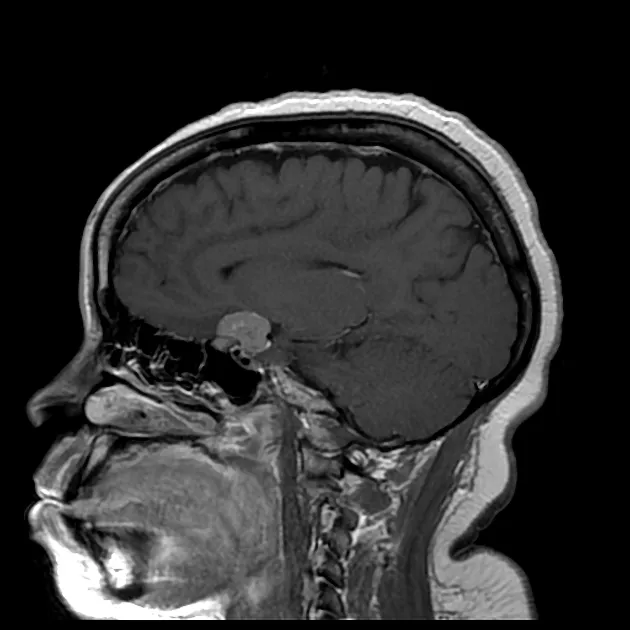

MRI sequences provide complementary information for tissue characterization and surgical planning. T1-weighted images demonstrate anatomy and gadolinium enhancement, T2-weighted sequences reveal tissue consistency and edema, while DWI differentiates cellular density and tumor grade.

CT imaging remains essential for bone evaluation and surgical planning. High-resolution CT with bone algorithms demonstrates cortical destruction, calcification patterns, and pneumatization variants. CT angiography evaluates vascular encasement and collateral circulation.

Clinical presentation patterns correlate with anatomical involvement and tumor biology. Pituitary adenomas present with hormonal syndromes (60-70%) or visual field defects (40-50%). Skull base meningiomas cause cranial neuropathies (70-80%) and headaches (60-70%).